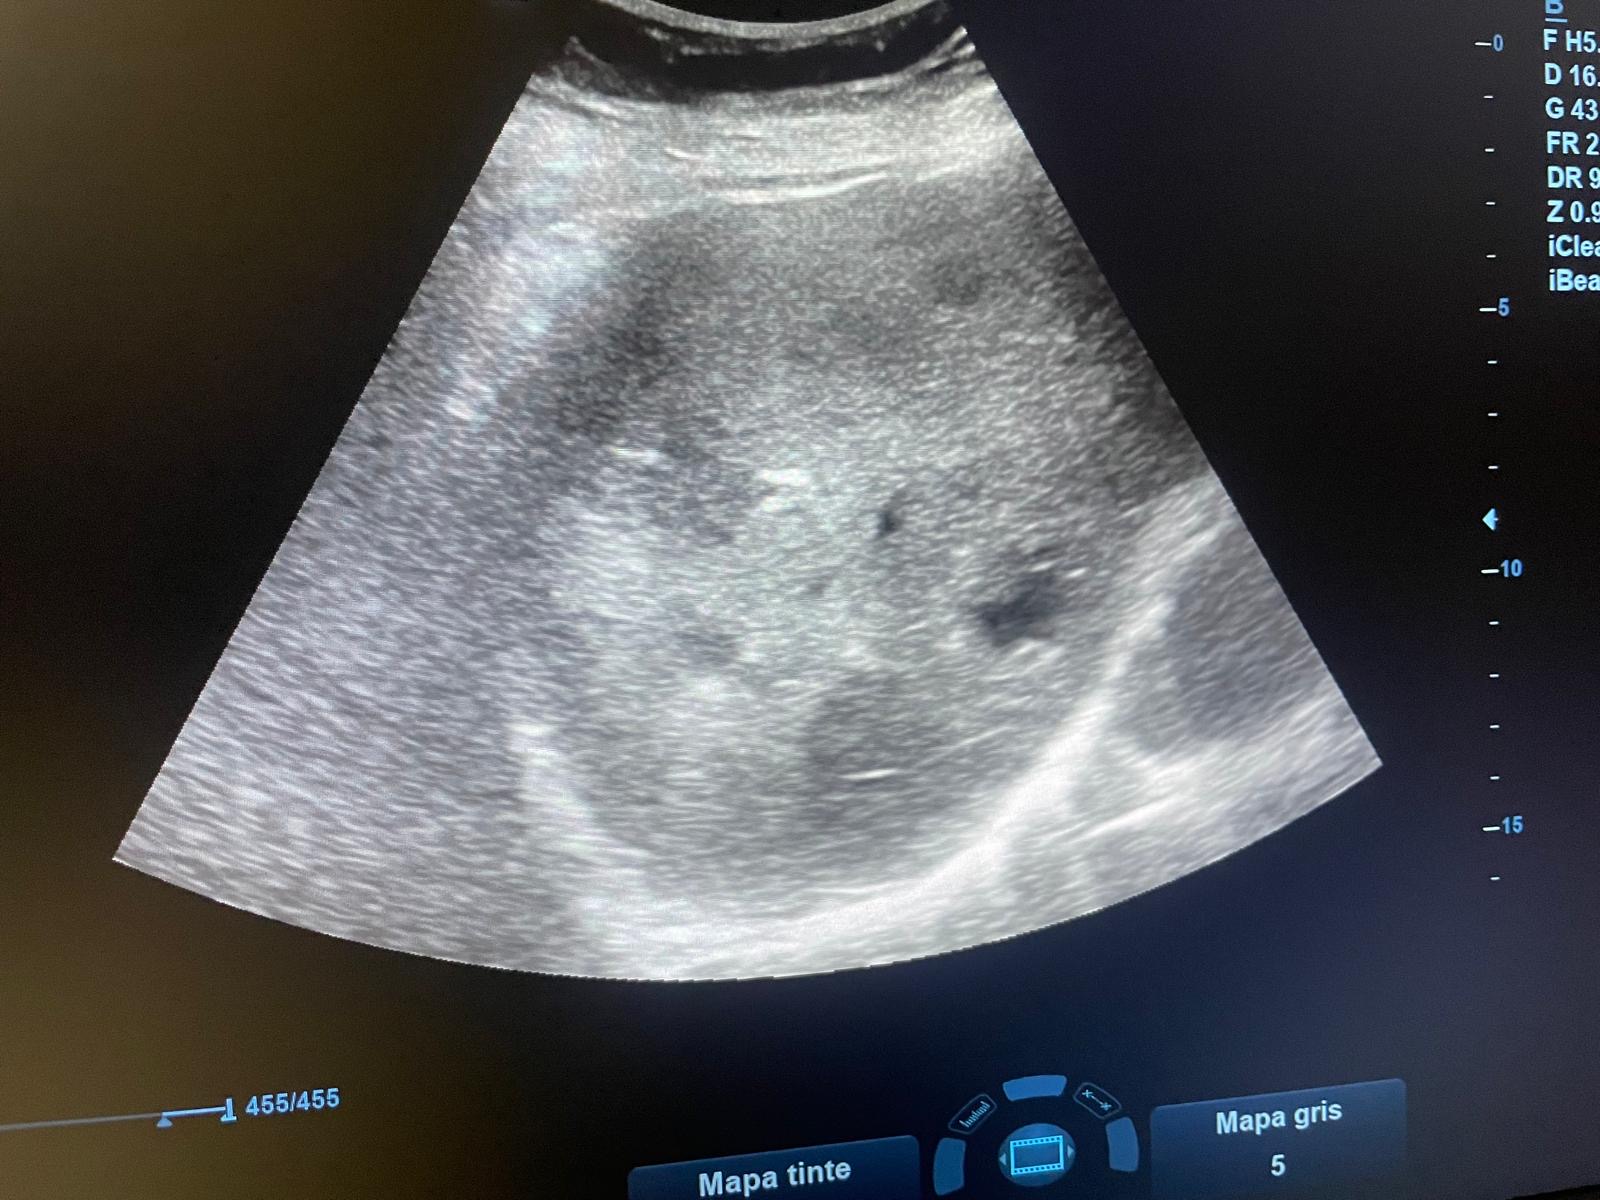

Paciente mujer de 96 años con antecedentes de HTA, DLP, DM tipo 2, cardiopatía isquémica que acude a consulta por cuadro de distensión abdominal, astenia, anorexia y hábito estreñido de dos semanas de evolución.Hallazgos ecográficos

Se realiza ecografía abdominal en la que se objetivan numerosas loes hepáticas heterogéneas algunas en ojo de buey sobre todo en cúpula hepática, sugerentes de metástasis hepáticas.Pruebas complementarias